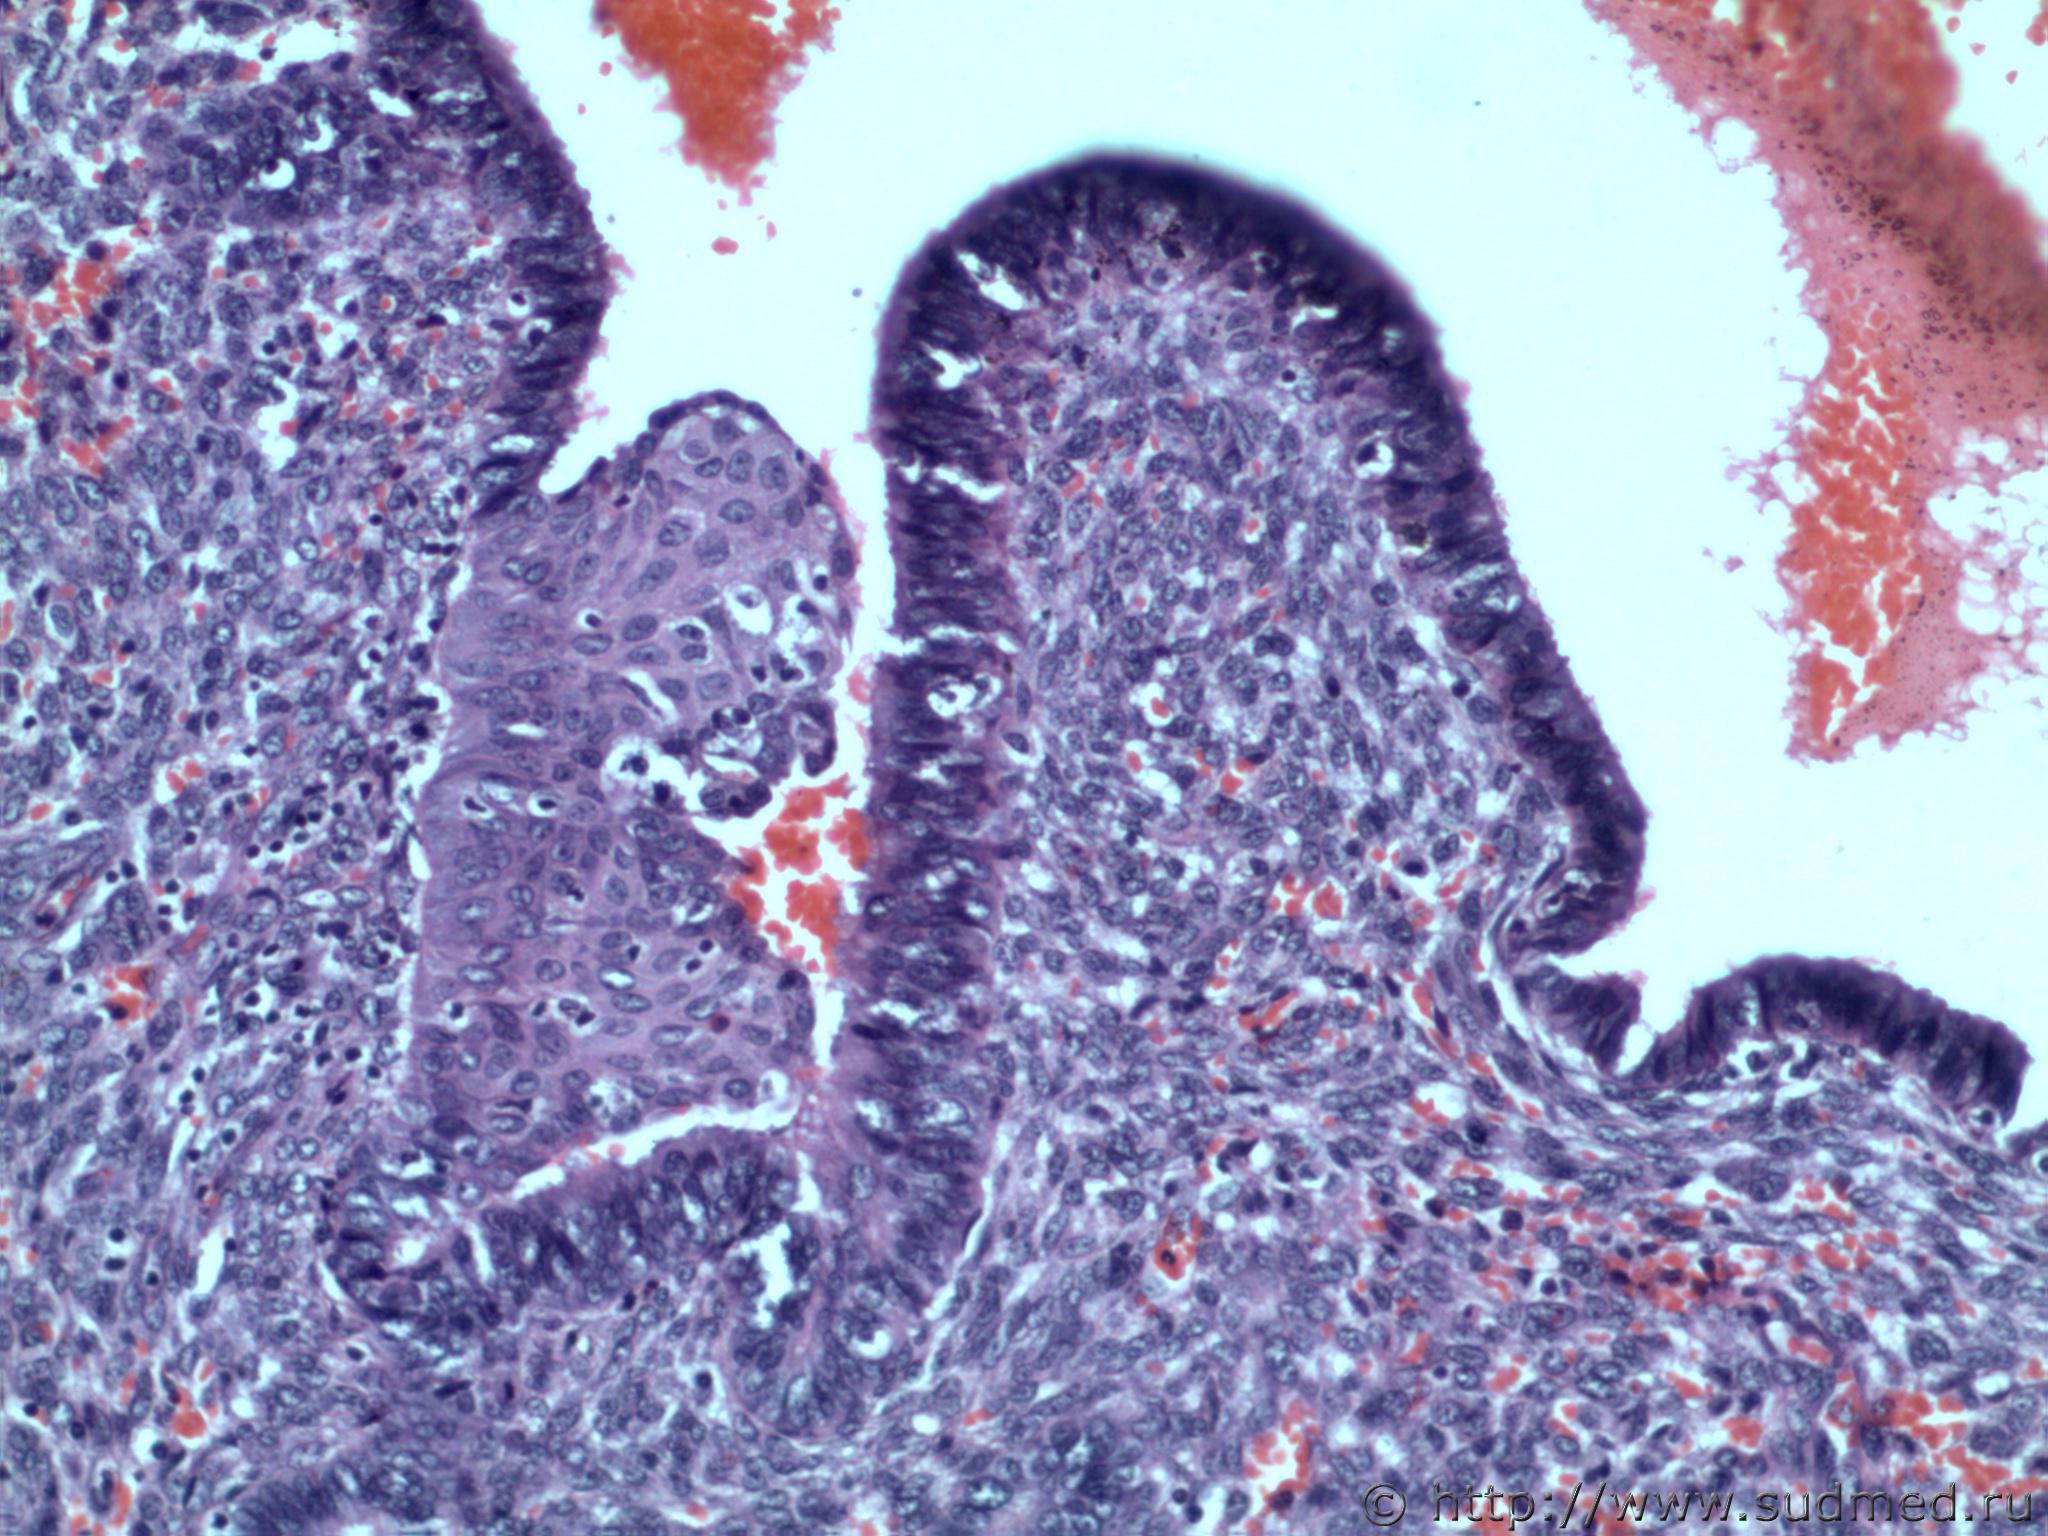

Трубная беременность (внематочная)

Плоскоклеточная метаплазия эндометрии